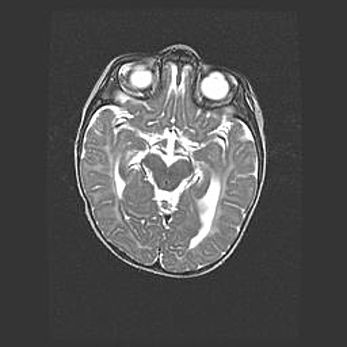

Лейкомаляция с кистозно-глиозной дегенерацией головного мозга.

Возраст: 2 месяца 25 дней

Вес: 6400 г

Окружность головы: 40 см

Срок гестации: 41 неделя

Лейкомаляцию относят к ишемически-гипоксическим повреждениям головного мозга, диагностируемым у новорожденных. При лейкомаляции в головном мозге обнаруживают очаги некроза, возникшие после тяжелой гипоксии и нарушения кровотока. В процессе морфогенеза очаги проходят три стадии: 1) развития некроза, 2) резорбции и 3) формирования глиозного рубца или кисты. Перивентрикулярная лейкомаляция (ПЛ) встречается примерно в 12% случаев среди новорожденных, обычно – у недоношенных детей, причем, частота ее зависит от массы, с которой младенец появился на свет. Наибольшее число малышей страдает лейкомаляцией, если масса при рождении 1500-2500 г.